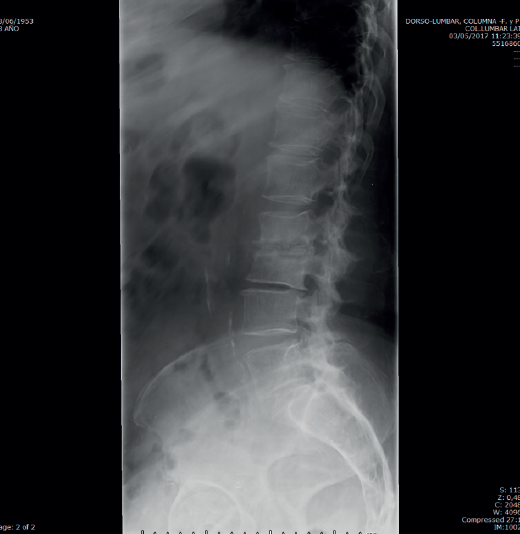

La analítica se había normalizado. En la radiografía lumbar (Figura 3) se veían signos de discopatía grave.